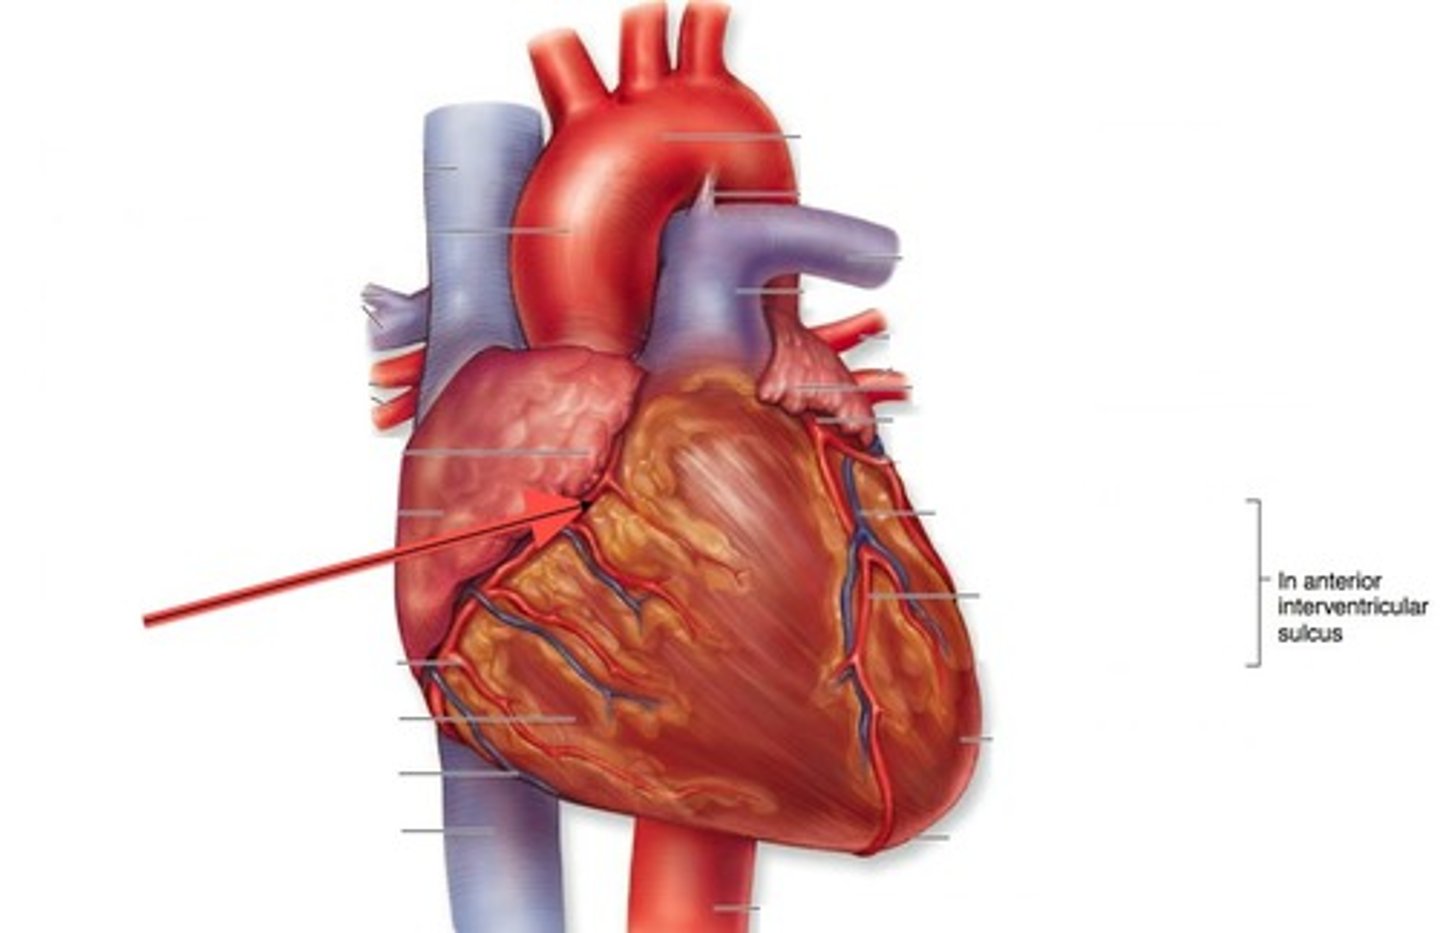

anterior interventricular sulcus

the junction between right and left ventricles

anterior side (depression)

anterior interventricular artery

in the anterior interventricular sulcus